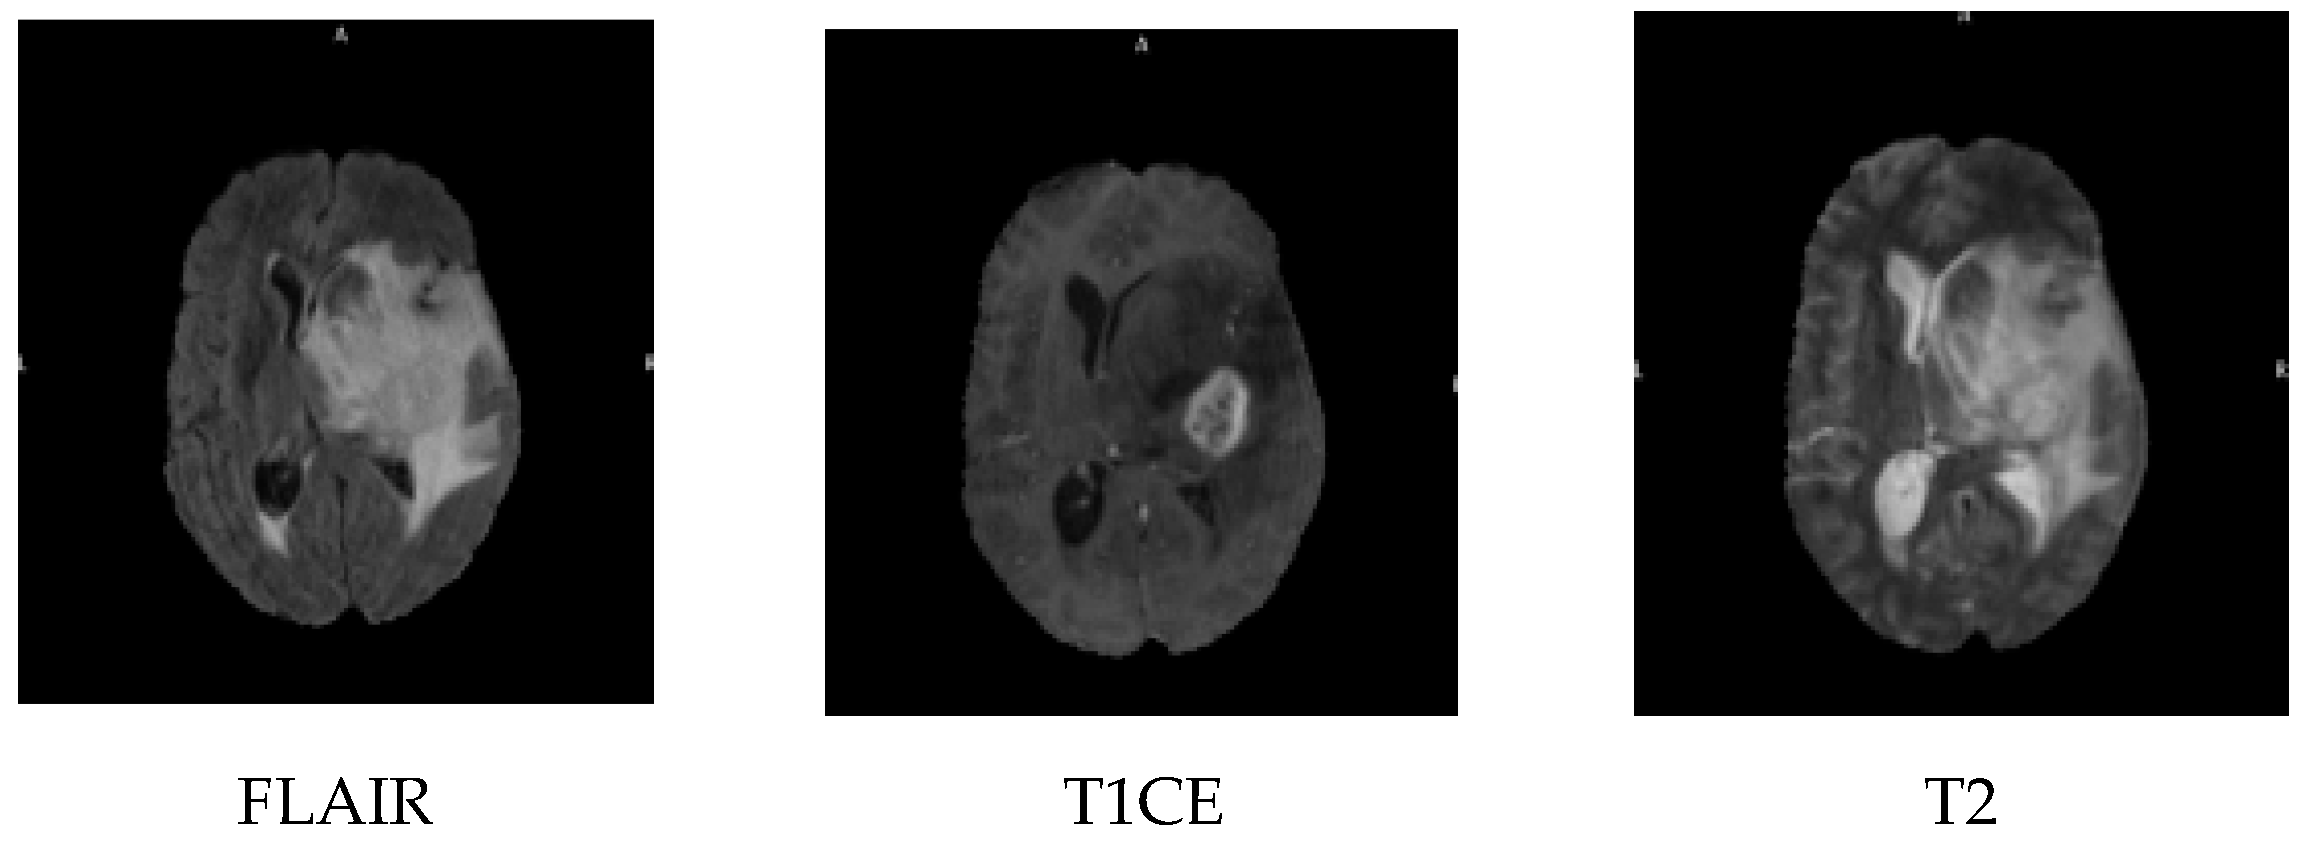

Radiological images are non-intrusive methods that avoid the use of ionizing radiation. Magnetic resonance imaging (MRI) is one of the most popular neuroimaging tools, as it provides three-dimensional images of the brain with excellent resolution and contrast [5]. MRI imaging is carried out in three planes, the sagittal, coronal and axial; the MRI sequences include contrast-enhanced fluid automation inversion recovery (FLAIR), T1-weighted with contrast enhancement (T1CE), and T2-weighted images, as shown in Figure 1. FLAIR is an MRI sequence that suppresses the signal from cerebrospinal fluid, making lesions more visible, especially in periventricular areas. T1CE imaging involves the use of a contrast agent, typically gadolinium, to highlight areas with a disrupted blood-brain barrier, such as active tumour regions. T2-weighted imaging provides high sensitivity to water content and is effective in identifying oedema and tumour-related swelling.

Figure 1. Magnetic resonance imaging sequences of the brain (left to right): FLAIR, T1CE, and T2 sequences.